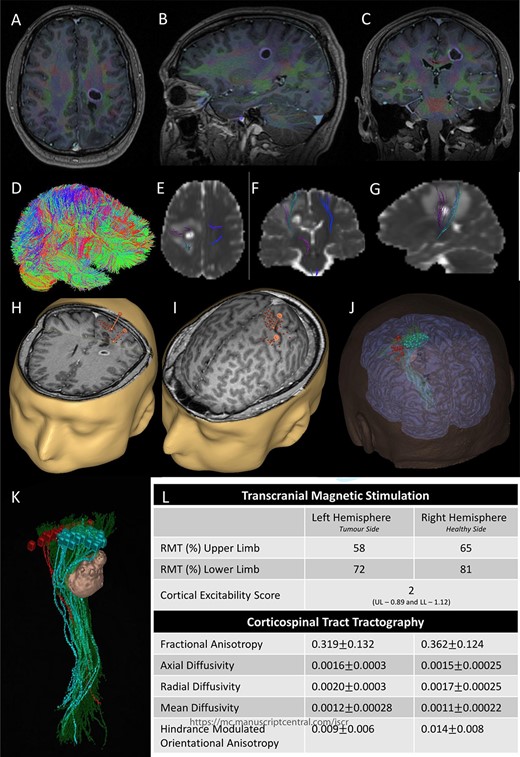

Integrated preoperative anatomical and functional brain mapping; (A–C) axial, sagittal and coronal fusion of T1-weighted MRI images with gadolinium and first eigenvector fractional anisotropy (FEFA); (D) whole brain tractography performed with StarTrack and visualized in TracViz according to deterministic spherical deconvolution algorithm. (E–G) fusion of CST with the ADC map; (H and I) nTMS mapping of the upper and lower limbs with hotspots for both upper and lower limbs identified with a marker (orange); (J and K) 3D Modelling of the tumour and the cortical and subcortical mapping of the CST with Stealth S8; (L) table summarizing the nTMS variables (resting motor threshold—RMT—and Cortical Excitability Score—Number of abnormal interhemispheric RMT ratios) and the tractography metrics.

Preoperative cortical and subcortical motor mapping was performed (Fig. 2). Diffusion tensor and spherical deconvolution tractography was used to delineate the anatomy of the CST bilaterally. Tensor-derived metrics were calculated for both CSTs. The fractional anisotropy and the hindrance-modulated orientational anisotropy of the left CST (tumour side) were lower. The axial, radial and mean diffusivities were higher in the left CST. Navigated TMS (NEXSTIM©; single pulse technique) was used to assess CST function. Abnormal interhemispheric RMT ratios (iRMTr) were found for both upper and lower limbs and an abnormal combined cortical excitability score (number of abnormal iRMTr)—2/2. This information suggested altered cortical excitability and microstructure of the CST on the side with the tumour.

Two independent techniques were used to dissect the ipsilateral CST with StealthViz Software (MEDTRONIC©): region of interest (ROI) technique and TMS-seeded technique. In the first one, two ROIs were defined, precentral gyrus and midbrain at the level of the superior cerebellar peduncle, the anatomical streamlines going through both regions were selected. In the second technique, the positive nTMS responses for the upper and lower limb were selected independently as ROIs and the other ROI was in midbrain at the level of the superior cerebellar peduncle. Both dissections of the CST were used as they provided an anatomical and functional assessment of the tract. The tumour was delineated in the Cranial Software (MEDTRONIC©) and the preoperative cortical and subcortical mapping was integrated in a 3D model (Fig. 2).